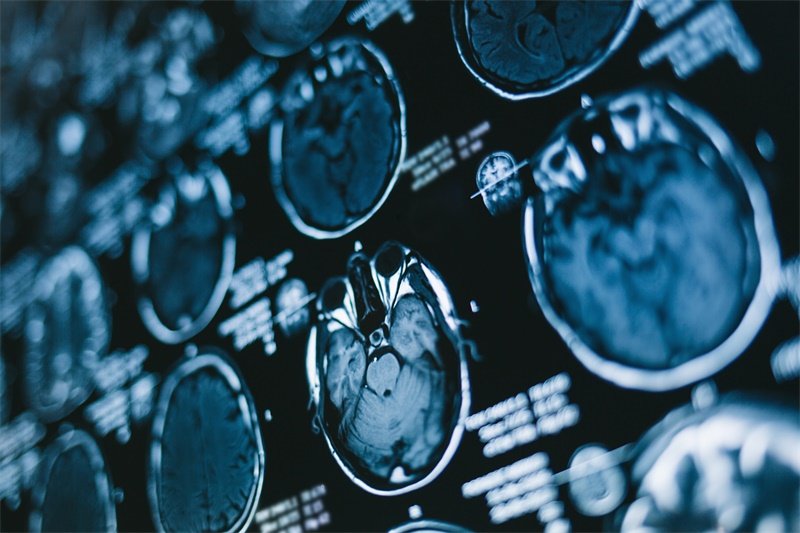

磁共振成像(MRI)

MRI是识别蝶鞍占位病变的重要工具,它可以清晰地显示病变的大小、位置和与周围结构的关系。通过图像的对比,医生能够更好地评估病变的性质。